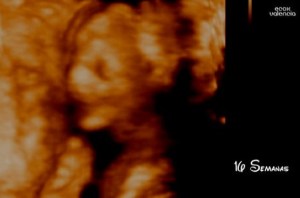

Ah, só pra publicar também, há duas semanas fizemos um ultra-som 4D e nos deram 70% de chance de ser menino e pelo que vi/pelo que me disseram quando chutam menino é certeiro. Por isso principalmente tenho falado “ele” pra cá e “ele” pra lá livremente! rs